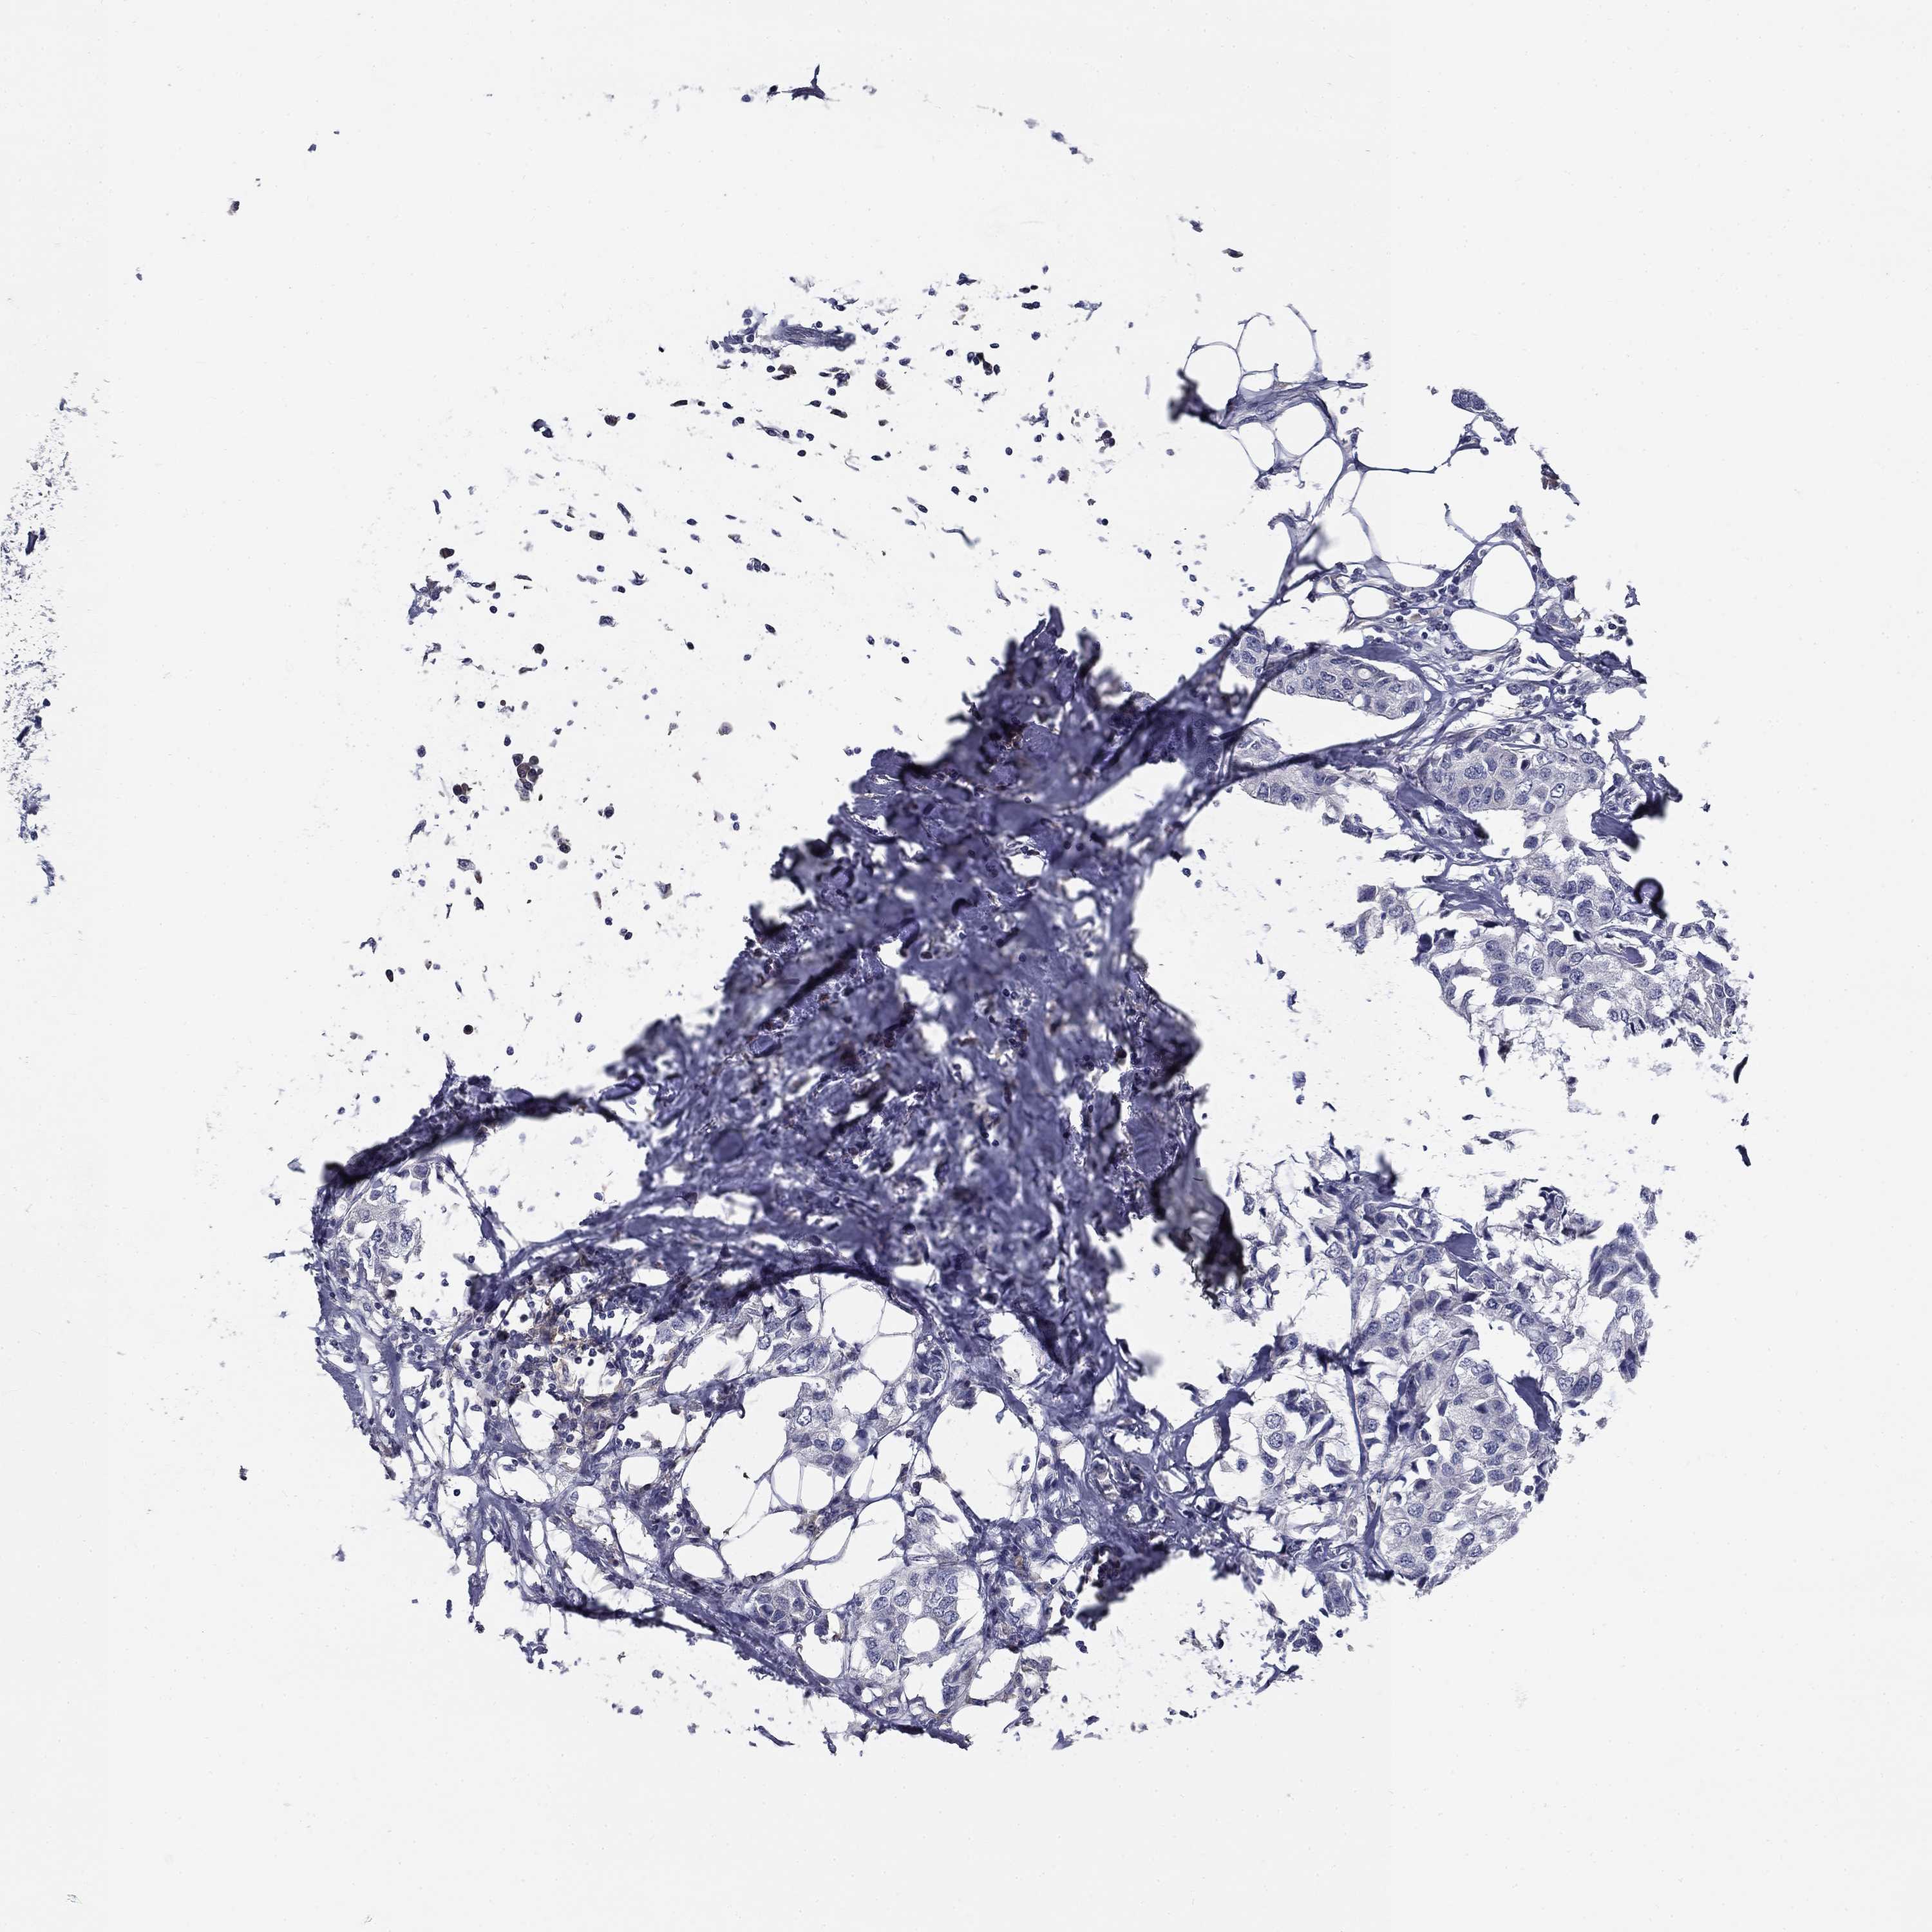

BRCA TCGA BRCA VALIDATION PROTEIN EXPRESSION

ANTIBODIES

AND

VALIDATION